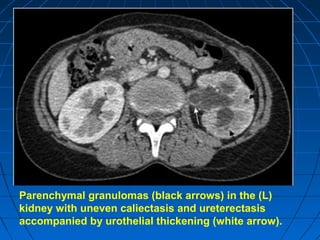

Parenchymal granulomas (black arrows) in the (L)

kidney with uneven caliectasis and ureterectasis

accompanied by urothelial thickening (white arrow).

Parenchymal granulomas (blackarrows) in the (L) kidney with uneven caliectasis and ureterectasis accompanied by urothelial thickening (white arrow).